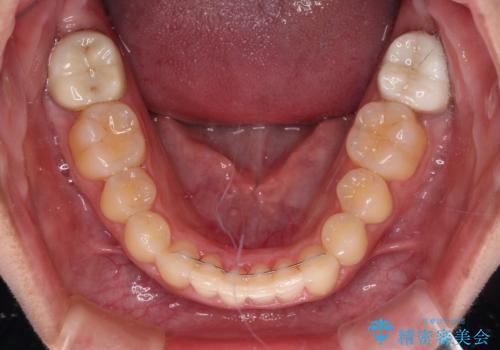

- 3年8ヶ月

- 上顎の重なっている前歯を気にして来院された患者様です。

八重歯改善には抜歯が必要で、八重歯の移動量が多く、更には右側にずれている正中を改善する必要がありました。

インビザライン単体での治療は困難と判断し、補助装置により八重歯移動後にインビザラインを用いることとしました。

インビザラインでは治療期間が延びることが予想されたため、ワイヤー矯正を提案しましたが、セラミッククラウンが多く、壊すあるいは傷が付く可能性があることから、長期間であってもインビザラインを選択されました。